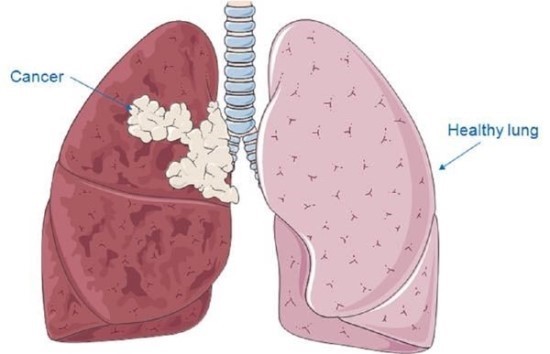

폐렴 증상 폐렴은 폐의 세균, 바이러스, 곰팡이 등 감염으로 인해

폐포(폐 속의 공기 주머니)에 염증이 생기고, 고름이나 액체가 차는 질환입니다.

이로 인해 산소 교환이 원활하지 못해 호흡곤란, 기침, 발열 등이 나타나죠.특히 영유아, 고령층, 면역력이 약한 사람에게서 더 위험하며